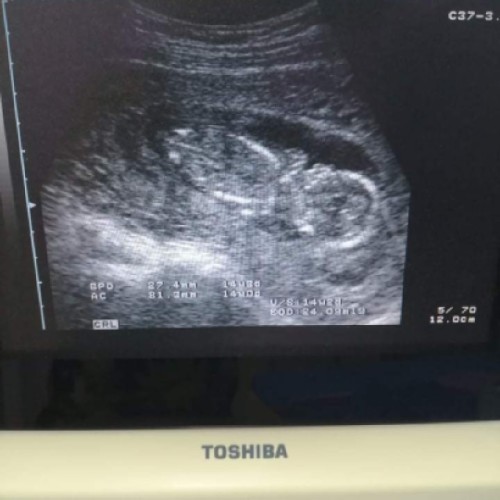

เพื่อนรุ่นน้องซาวด์ตอน 13 วีค ท้องได้ 3เดือนกว่าคุณหมอบอกว่าลูกดิ้นแล้วเเต่ทำไมคุณเเม่ไม่รู้สึกเลย หรือเป็นเพราะขนาดตัวลูกยังเล็กมาก เเละอย่างนี้ลูกผิดปกติไหมค่ะ

เรา13wเมิ่ลกันค่ะ. รุ้สึกได้เป้นบางรั้งบางคราว ได้ เหนหัวใจเค้าเต้น แสดงว่าเค้ายังแรงแข็งดีค่ะ

บ้านนี้ไปซาวด์ตอน 14วีค3วัน หมอบอกลูกดิ้นเก่งมาก ตอนนี้16วีคแล้วยังไม่รู้สึกเลยค่ะ

คุณหมอบอกดิ้น ลูกดิ้นให้เห็นตอนซาวค่ะ แต่น้องตัวเล็กมากคุณแม่เลยยังไม่รู้สึก